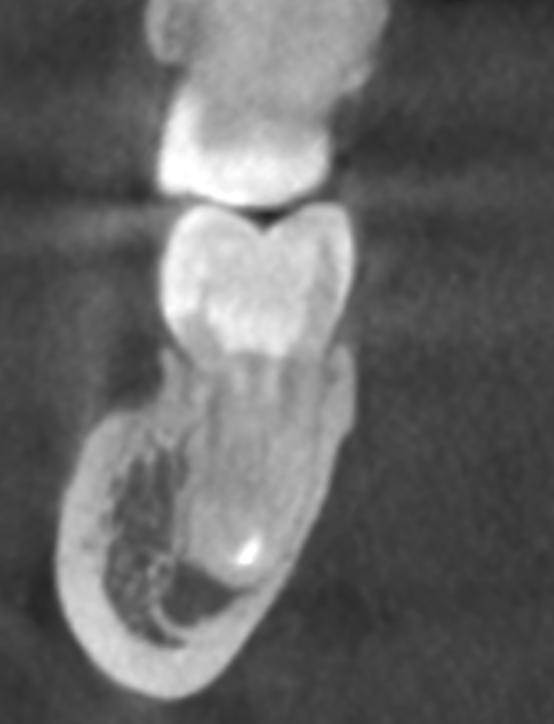

Гарриевич Опубликовано 31 января Автор Поделиться Опубликовано 31 января Когда в твоем кресле оказывается пациент с редким заболеванием «стоматолог-терапевт» работать всегда… легче. Именно! Потому что ты на 100% уверен, что этот человек понимает разницу между «гарантия» и «прогноз», а он на 100% уверен, что ты тот кто ему нужен. Зуб 4.7 со сложной анатомией, ступенькой в мезиальной системе, двойным изгибом, пропущенным каналом и апикальным периодонтитом. Реколл 1 год И сам осмотр через 1 год 4 1 1 Ссылка на комментарий